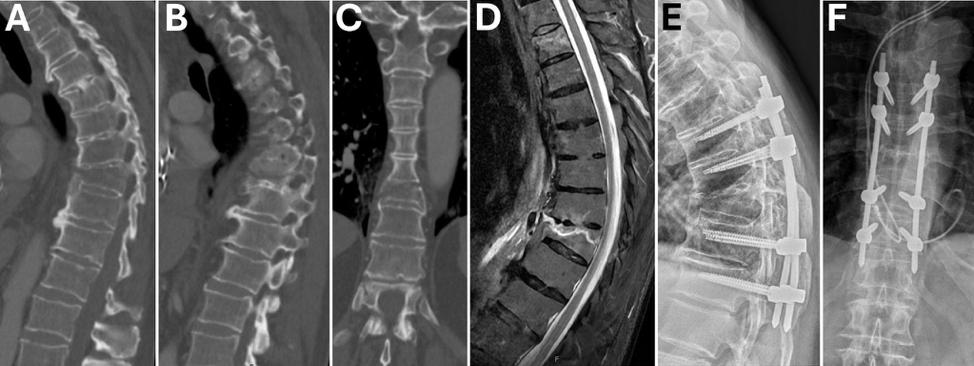

A 71-year-old man with ankylosing spondylitis sustained a mechanical ground-level fall that resulting in an extension injury involving the anterior and middle columns of T9, as seen on CT and MRI (Figure 1AD). He underwent percutaneous T7-T11 instrumentation to stabilize the injury (Figure 1E and F).